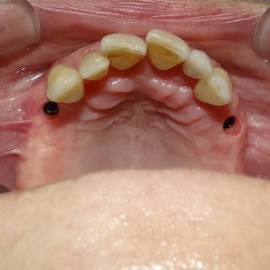

Pacjentka głosiła sie do naszego gabinetu do leczenia z osadzonym mikroimplantem w pozycji lewej dolnej dwójki. Siostrzany implant w pozycji prawej dolnej dwójki wypadł wcześniej, około 1,5 roku od implantacji. Odtworzono przedsionek i dziąsło rogowaciejące, osadzono dwa implanty, jednoczasowo z regeneracją kości. Dopiero na etapie ostatecznej rekonstrukcji protetycznej usunięto zachowany mikroimplant. To się nazywa motywacja do leczenia! Pacjentka przygotowywała sie na ślub prawnuczki :)